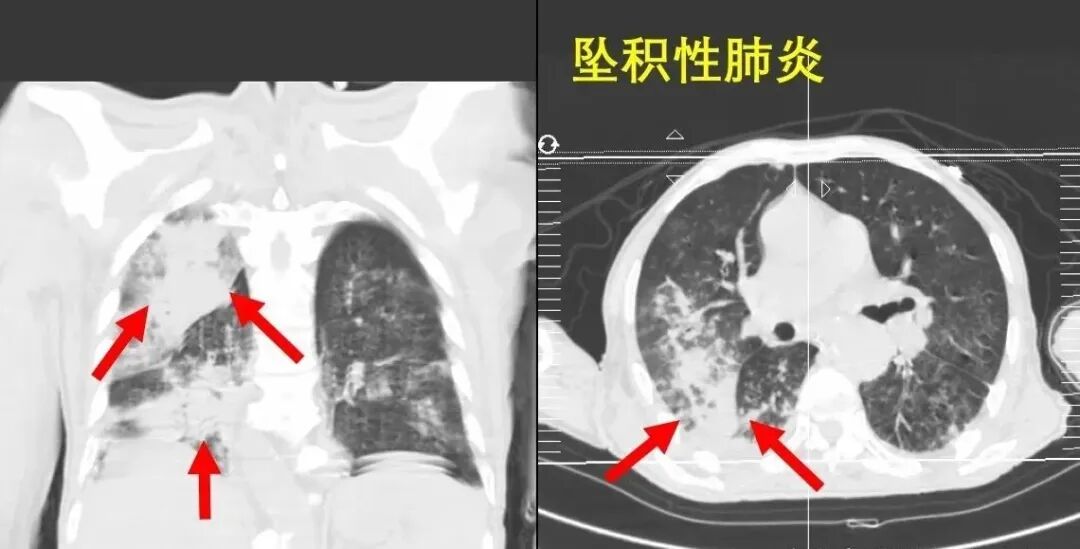

骨折本身并不致命,最大的风险来自各种并发症,尤其是坠积性肺炎。

图片

1.坠积性肺炎。简单来说,我们很多人早上起床都会清嗓子吐痰。如果长时间卧床,痰会沉积在体内。老年人呼吸功能较弱,骨折后,他们不敢吐痰,甚至因为疼痛也不敢深呼吸。痰不能从体内排出,因此产生的肺部感染严重的可能导致死亡。